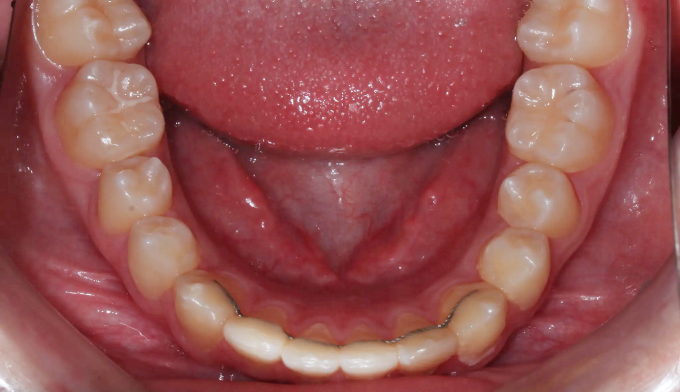

이번 케이스에서는 위쪽 송곳니의 맹출경로이상, 아래쪽 작은어금니는 작은 물혹으로 인해 맹출 경로에 문제가 생겨 교정을 진행한 경우입니다.

물혹을 제거하고 치아 교정장치를 부착하여 간단히 배열하였습니다.